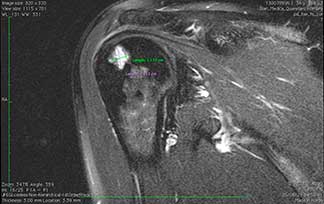

Quiste Óseo subcondral en cabeza de húmero derecho, imagen por resonancia magnética.